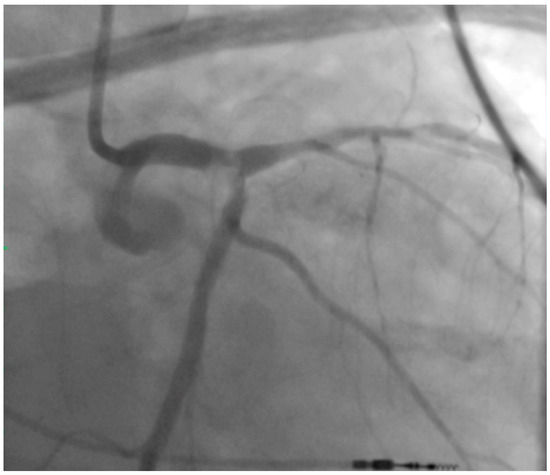

2. Left Main PCI

4. Achieving Adequate Left Main Minimal Luminal Area

5. Atherectomy in UPLM PCI